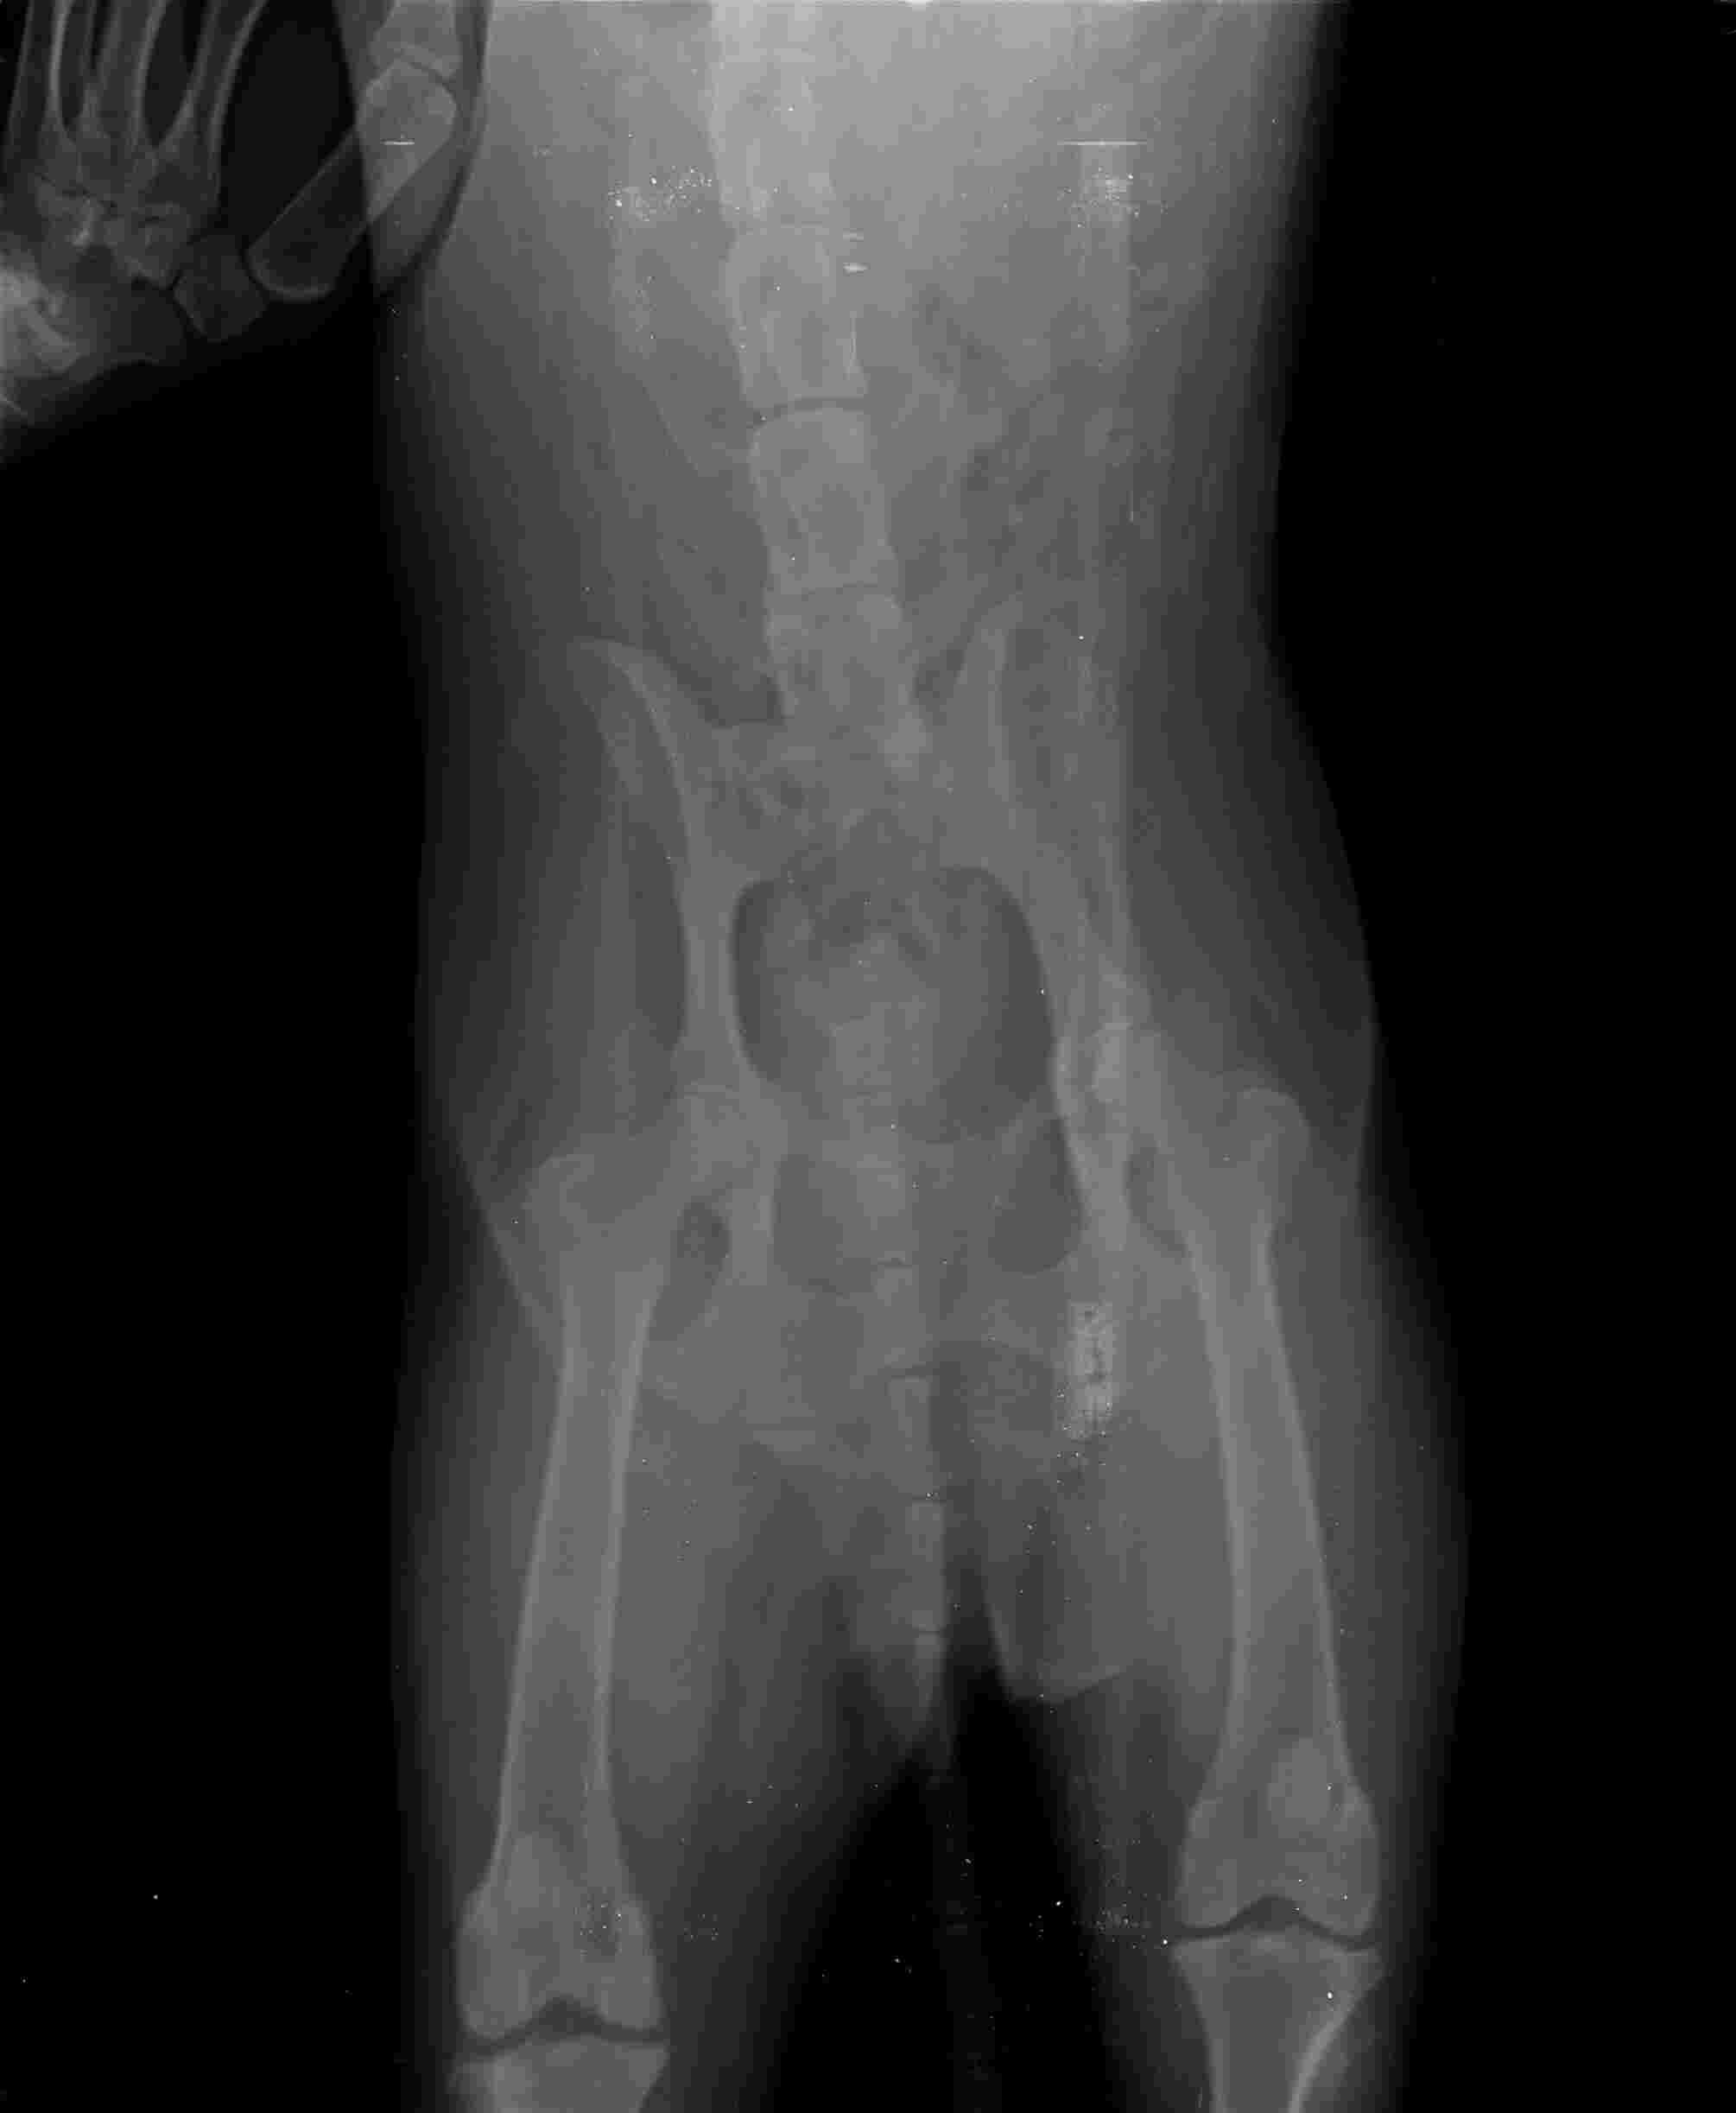

Hello, i have a husky female, she is 9 years old, in december she had the operation spayed and removal of a tumour in her breast in the same time both of them, since then the walking was not that good anhmore she barely could of and in the same time we went visitong her and she has arthrithis, now she barely can stay she can not walk anymore plase tell.me what can i do beside painkillers and supplements, i need some natural organic treatments a quick one please help

This question includes photos that may contain sensitive content. Click to view.